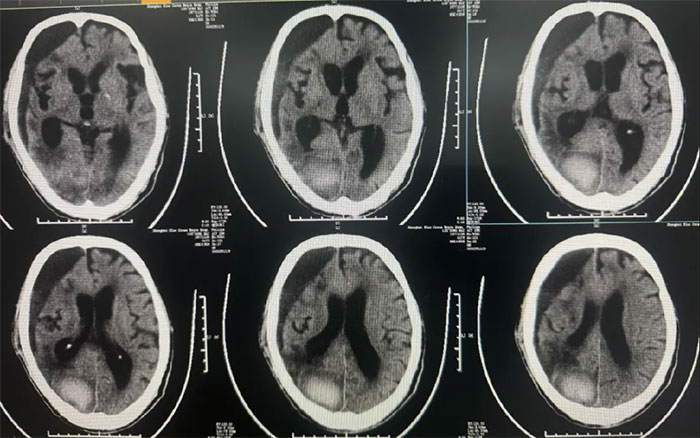

术后中线偏移明显改善,颅内压降低,停用脱水药物;

● 硬膜下血肿引流15天后拔管,中线基本复位,硬膜下血肿较前明显减少;

● 患者神志昏迷,自动睁眼,无发声,肢体刺痛躲避。GCS评分:9分;

● 无明显颅内感染,生命体征平稳。